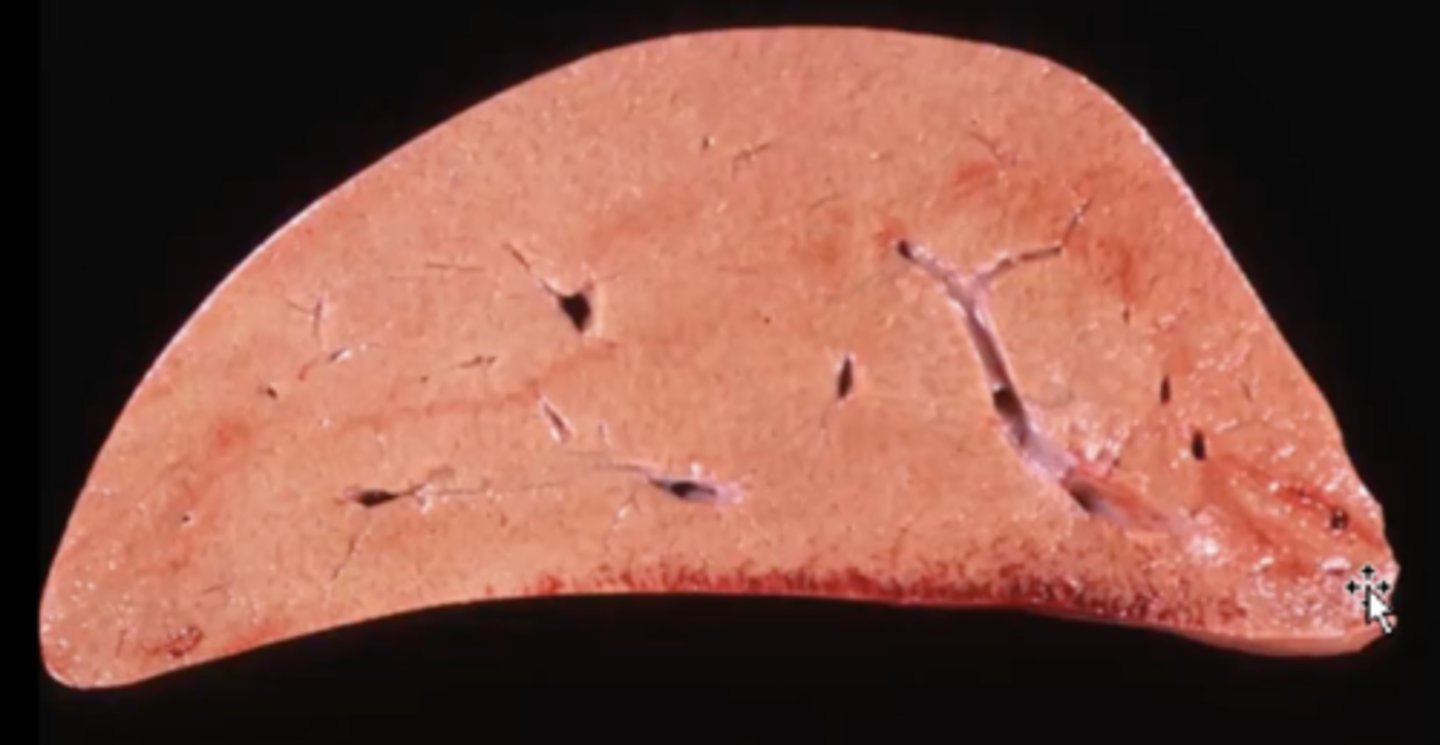

Milk spots - scars from ascaris suum migrating through the liver

Pig liver: What are these white sunken spots known as ?